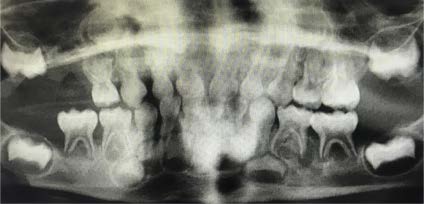

The panoramic dental radiograph from the patient’s dentist visit 2 weeks earlier was obtained (Figure 3), and an oral mucosal biopsy was performed after concerns about possible abnormal soft tissue in the gingiva and lytic lesions around the mandibular molars. CT scan of the mandible, performed in the hospital after these images were received, confirmed mandibular lytic lesions.

Figure 3. Panoramic dental radiograph taken at a dentist visit 2 weeks before presentation showed poorly visualized mandibular lytic lesions.

CT scans of the mandible and noncontrast panoramic dental radiographs showed periodontal osseous erosions and lytic lesions of the mandibular molars and osseous erosion at the dental fossa base, possibly representing an early oral antral fistula. Magnetic resonance imaging of the brain was performed, the results of which were negative for lesions suspicious of LCH but showed mild paranasal sinus disease and opacification of the mastoid air cells. Echocardiography findings were normal.

Pediatric SP has many differential diagnoses including simple viral, bacterial, or fungal infections; CF; LCH; Marfan syndrome; and malignancy.7,10,11 LCH can present in many ways, including SP. Lung findings can be seen in the absence of clinical pulmonary symptoms, so it is vital to be familiar with alternative presentations, such as in bone as illustrated in Figure 3.9,10 If there is enough suspicion to warrant imaging, a CT scan can provide clues to anticipate future episodes of PSP.8 Counseling on long-term management of any lung pathology in children is warranted.6 Smoking cessation, as evidenced among pregnant women with LCH, appears to be a critical factor impacting the course of the disease.6 Follow-up and long-term prognosis of SP is dependent on etiology, and treatments will differ accordingly.